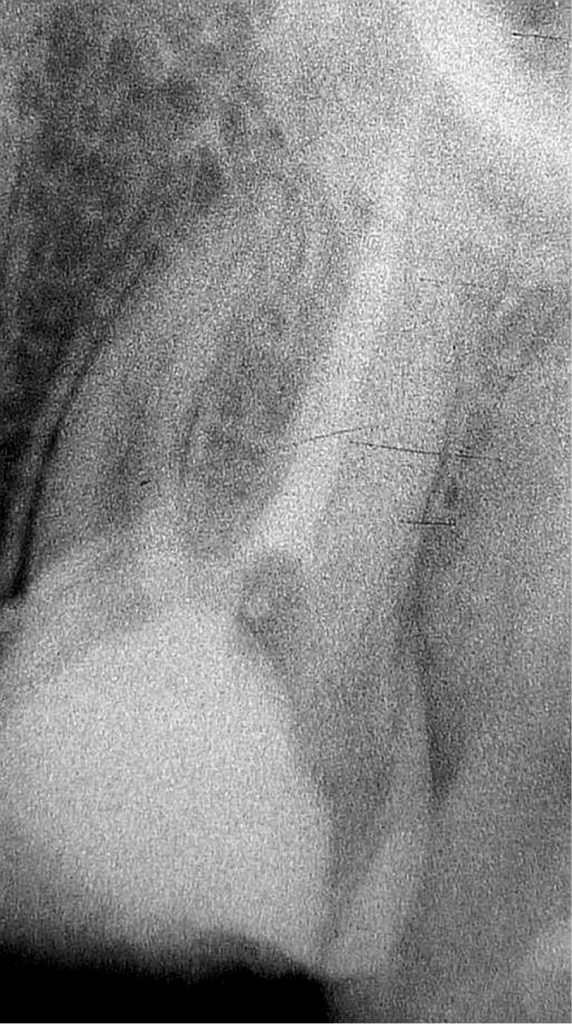

- Jak usunąć złamany instrument? Opisy poszczególnych technik.

Streszczenie: Endodoncja i jej rozwój na przełomie ostatnich lat daje coraz większe możliwości na zachowanie zębów własnych pacjenta. Na uwagę zasługuje fakt radzenia sobie z powikłaniami leczenia endodontycznego, które, mimo udoskonalonego sprzętu, techniki stosowanych materiałów i wiedzy lekarza, są nieuniknione. Omawiając problematykę usuwania złamanych instrumentów z kanałów korzeniowych, na podstawie piśmiennictwa przedstawiono nowoczesne techniki ich usuwania. W artykule opisano główne przyczyny i konsekwencje złamań. Przedstawiono, co wpływa na sukces (powodzenie) zabiegu oraz jak można zminimalizować ryzyko złamania instrumentu endodontycznego.

Summary: Endodontics and its development in the last years offers repeatedly better opportunities for saving patient’s own teeth. Dealing with endodontic treatment complications, which in spite of refined equipment, materials applied and medical knowledge are inevitable, deserves attention. Current techniques of broken instruments removal were reviewed, focusing on removing broken instruments from root canals. Main causes and consequences of fractures were described [...]